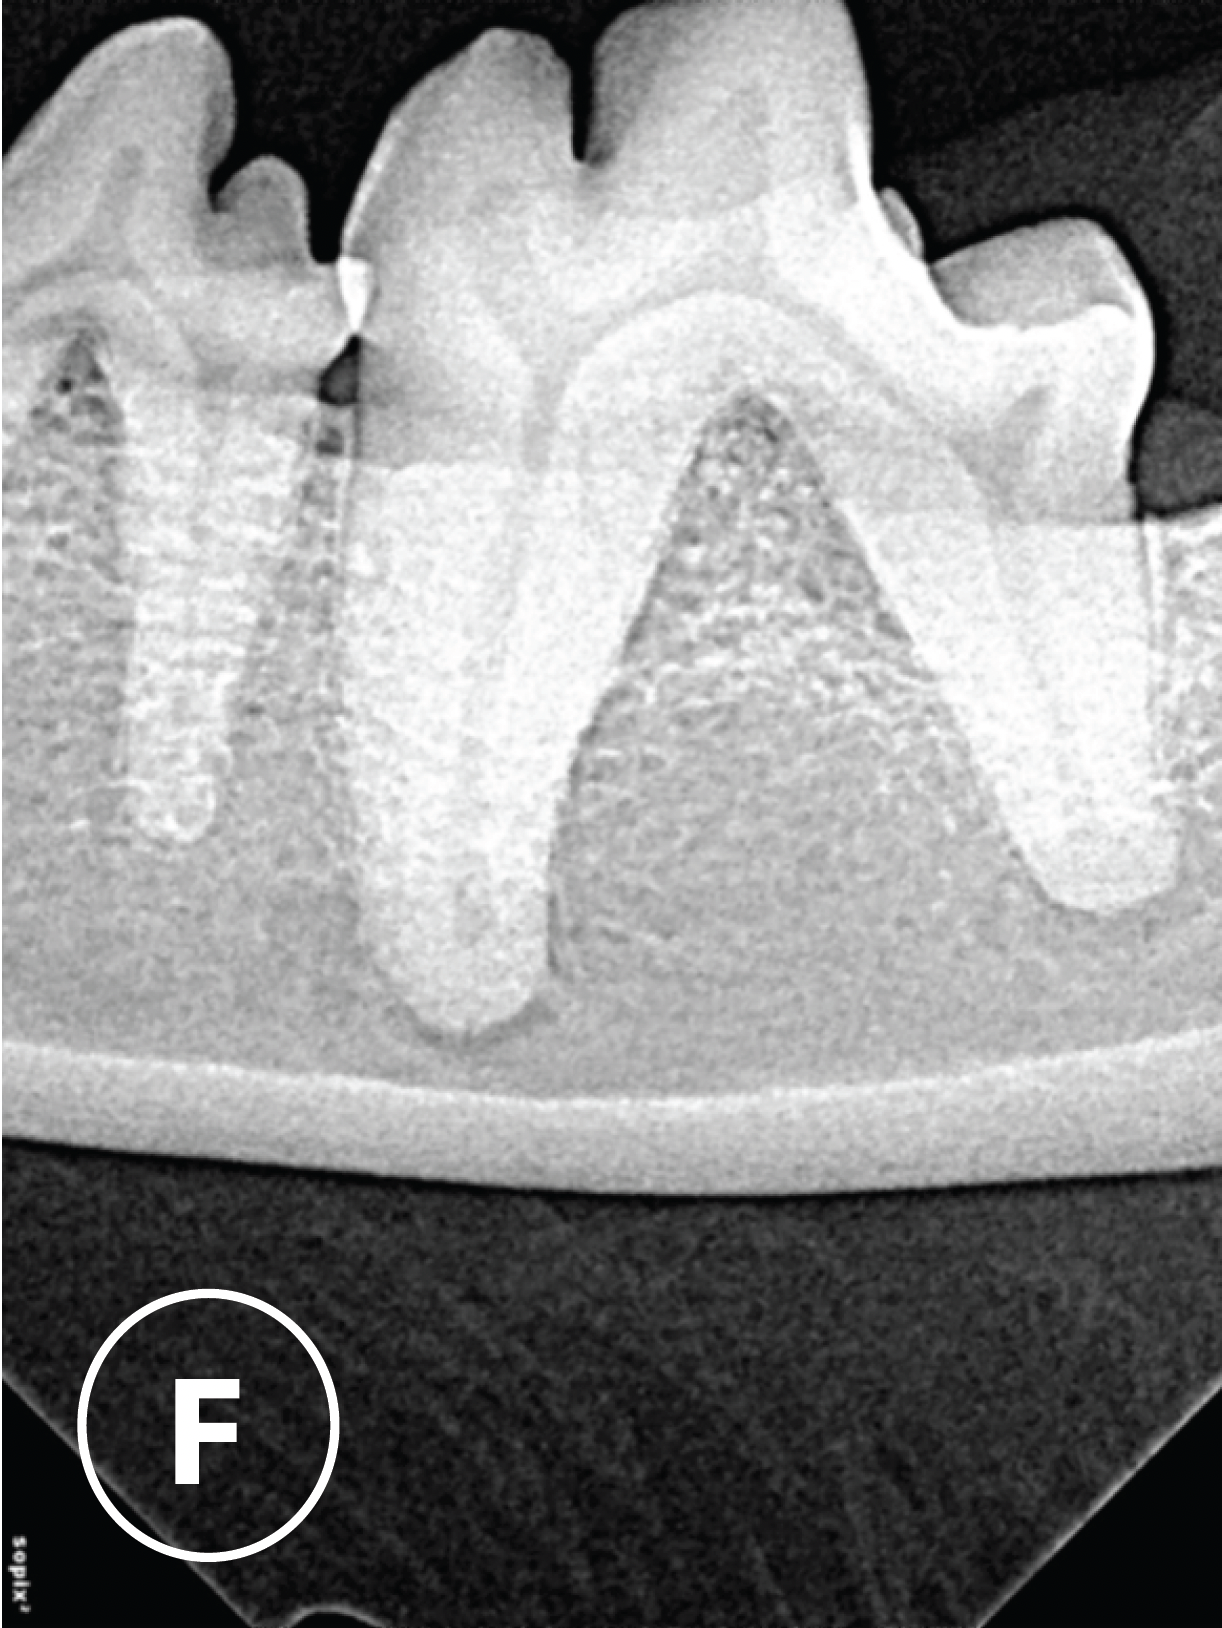

6 month post-treatment radiographs

H & I : Radiographs of 309, 6 months post placement of bone graft, demonstrated new bone formation within the furcation defect and some increase in alveolar bone height adjacent to the furcation.